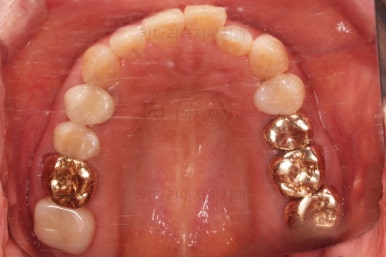

최종 사진을 보여드리겠습니다.

깔끔하게 마무리가 되었네요.

전후 비교입니다.

환자분도 치료에 만족하시어 미적으로 보기싫은 다른 금니들도 하나씩 교체하고 계신 중입니다.